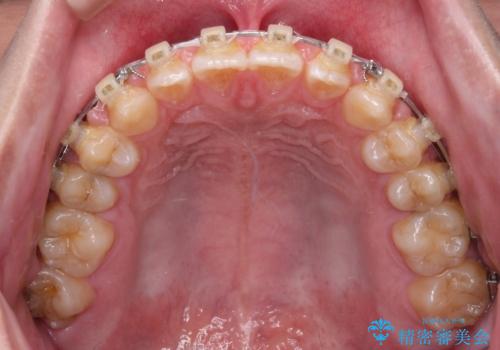

空隙歯列を閉じる 舌のトレーニングとワイヤー矯正

- 上下前歯の隙間を気にして来院された患者様です。

飲み込みや話をするときに舌を突出させる癖が強くあり、それが原因でスペースが空いていました。

舌癖を改善するためのトレーニングを行いながら、ワイヤー装置を用いて前歯の隙間を閉じていくこととしました。

舌の突出癖がなかなか改善されず、治療期間は当初予定よりも大分長くなりました。

装置除去を予定していた日に、油断されたのか1mmほどのスペースを作ってしまったため、除去が3ヶ月延長されたことで、舌のトレーニングの重要性を理解していただきました。

装置除去後もトレーニングを継続されているようで、後戻りによるスペースは今のところ認められておりません。